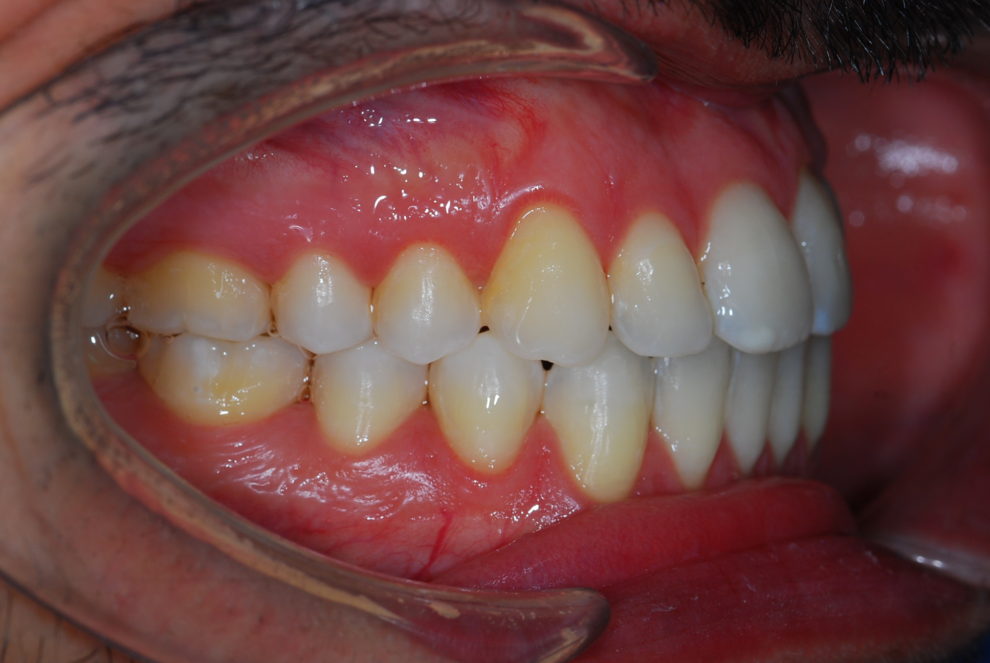

Ortodoncia + Mordida abierta

Nuestro paciente Manuel Vergara Gil acudió a nuestra clínica, y se le hizo una Ortodoncia.